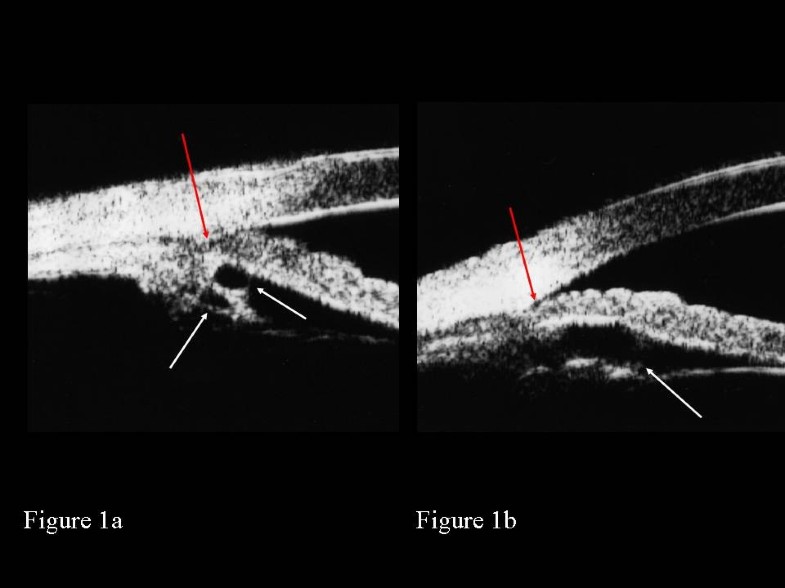

A) After laser peripheral iridotomy, ultrasound biomicroscopy showed Laser Peripheral Iridotomy (Lpi) Side Effects  However, laser iridotomy has low risk of side effects and is a very safe procedure that prevents a potentially devastating eye. Cataract formation, visual dysphotopsias (glares, halos, lines, spots). Possible risks include, rise in eye pressure, bleeding at the laser site, and inflammation; Minor complications of laser iridotomy, such as inflammation, usually resolve within a few days after surgery with. Laser Peripheral Iridotomy (Lpi) Side Effects.